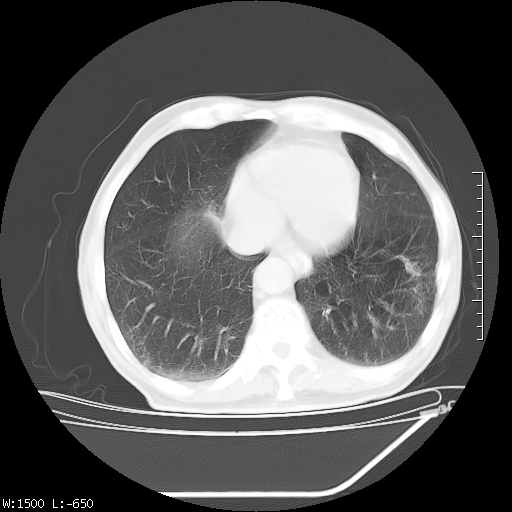

标题: CT23994:男、72、咳嗽、气短两月余,近来消瘦。 [打印本页]

标题: CT23994:男、72、咳嗽、气短两月余,近来消瘦。

右上肺实变,与胸膜关系密切,右肺容积缩小,隆突下淋巴结增大,考虑1 肺结核 2 肺癌

tb可能性大(双肺均可见片状密度增高灶,其内可见低密度空洞)。

右上肺大片状密度增高影,与胸膜关系密切,内见低密度透亮影,胸膜下可见三角形不张影,左下肺沿支气管走形结节影,纵膈内淋巴结显示。考虑结核并疤痕性不张可能性大,建议穿刺活检,排除肺泡癌。